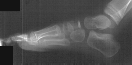

RADIOGRAPHS : AP, lateral and oblique views bilateral feet demonstrate

bilateral avascular necrosis of the navicular.

RADIOGRAPHIC FINDINGS

- flattening of the navicular

- narrowing of the navicular AP diameter in the lateral view

- irregular rarefaction and sclerosis

- irregular ossification of the navicular is seen in normal feet

- diagnosis of Kohler's disease should only be made when symptoms are

present